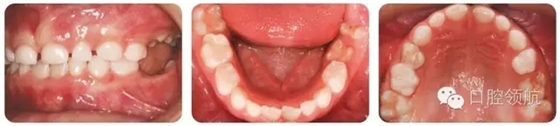

圖2.10的上頜牙列特征有哪些?

圖2.10

早期恒牙列患者,UL3腭側(cè)錯位萌出。左上頜乳尖牙滯留。UR6輕度發(fā)育不全。